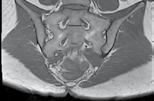

Figura 1: Cazul unei femei de 66 de ani, cu probleme de sănătate complexe, care a suferit o fractură patologică la nivelul humerusului din cauza unei metastaze. (A) Evidențiază metastaza osteolitică din humerus. (B) Imagine scintigrafică ce arată răspândirea sistemică. (C) Imagine postoperatorie care prezintă o tijă centromedulară utilizată pentru osteosinteză, permițând mișcarea imediată a brațului.